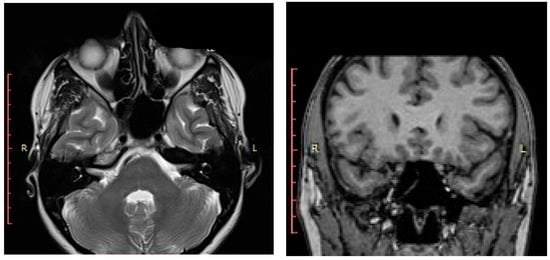

The computed tomographic (CT) examination described a 32 × 28 mm pseudo-cystic lesion in the left sphenoid sinus that occupied approximately 80% of the sinus cavity, in close relation with its posterior wall. The lesion was located within the sinus cavity without extension into the sphenoethmoidal recess or the nasopharynx. No bone erosions were visible on the imaging. All other paranasal sinuses appeared well aerated and tumor-free (Figure 1a–c). The CT assessment also highlighted the nasal obstruction with left posterior nasal septum deviation that determines blockage of the left sphenoethmoidal recess and bilateral inferior turbinate hypertrophy.

Figure 1. CT of the paranasal sinuses - (a) axial, (b) coronal, and (c) sagittal planes—lesion in the left sphenoid sinus.